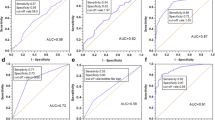

The percentages of the low risk CANARY component were significantly higher in AIS than MIAs (P=0.034), in AIS than IACs (P<0.001), and in MIAs than IACs (P=0.024). The percentages of the intermediate risk component were significantly lower in AIS than MIAs (P=0.037), in AIS than IACs (P<0.001), and in MIAs than IACs (P=0.016). The percentages of the high risk group were significantly lower in AIS than in MIAs (P=0.037), in AIS than in IACs (P<0.001), and in MIAs than IACs (P=0.002).

The relations of the size of the invasive focus and the volumes of the intermediate and high risk components were statistically significant (r=0.477, P<0.001, and r=0.471, P<0.001, respectively). However, the relation of the size of the invasive focus and the volume of the low risk component was not statistically significant (r=0.200, P=0.679). The relations between the percentage of the three CANARY components with the size of invasive focus were statistically significant (low risk: r=-0.406, P=0.005; intermediate risk: r=0.407, P=0.005; high risk: r=0.467, P<0.001), respectively.

Individual percentages of the low risk group are displayed in Fig. 5. For each threshold value, sensitivity, specificity, NPV, and PPV are shown in Table 2.

Individual percentages of the CANARY low risk components for non-invasive (adenocarcinoma in situ) and invasive (minimally invasive adenocarcinoma and invasive adenocarcinoma) groups Note.- AIS- adenocarcinoma in situ; MIA - minimally invasive adenocarcinoma: IAC- invasive adenocarcinoma; Sens – Sensitivity; Spec- Specificity; PPV-positive predictive value; NPV – negative predictive value

Individual percentages of intermediate risk group are shown in Supplementary Fig. 1.